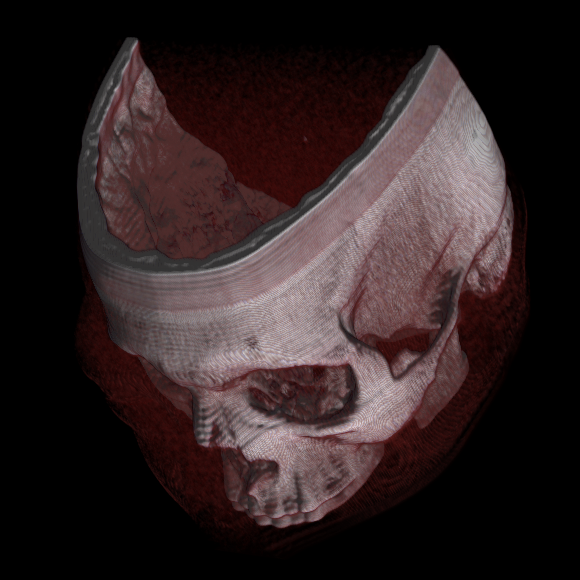

이미지 분할은 렌더링 전에 관심 없는 볼륨의 큰 부분을 잘라내는 데 사용할 수 있는 수동 또는 자동 절차이며, 광선 추적 또는 텍스처 혼합으로 수행해야 하는 계산량을 크게 줄일 수 있다. 이 감소는 순차적으로 인덱싱된 복셀 n에 대해 O(n)에서 O(log n)까지 될 수 있다. 볼륨 분할은 다른 광선 추적 알고리즘에도 상당한 성능 이점을 제공한다. 볼륨 분할은 그 후 관심 구조를 강조하거나 노출하는 데 사용될 수 있다.